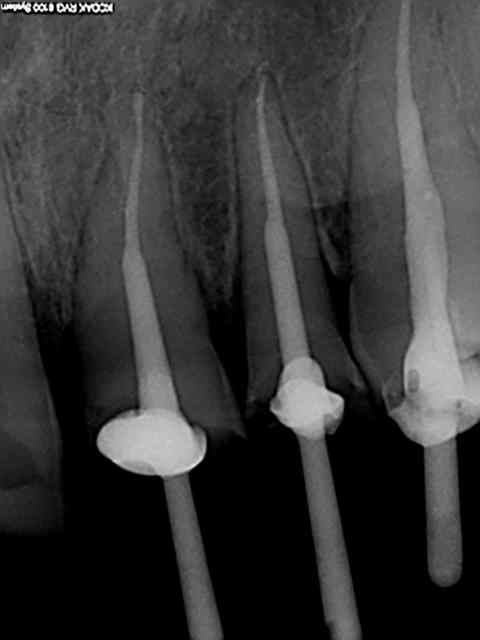

J'ai terminé la moitié de ma boite de gutta avec ce patient .

Img 5415 n0e23w - Eugenol